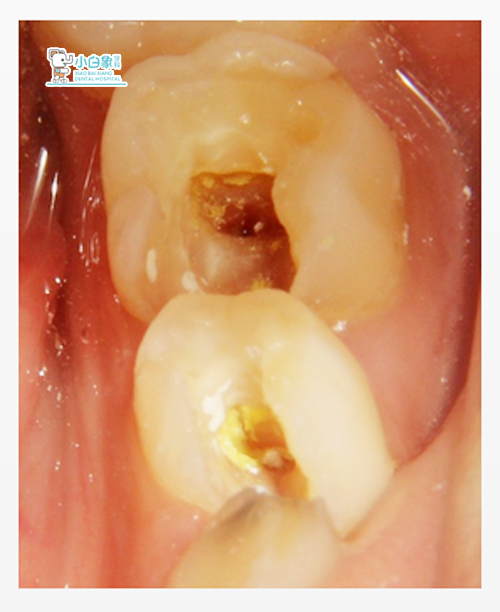

检查:75近中邻合面龋坏达髓角,叩诊(++),温度试验无反应,

颊侧牙龈红肿。

诊断:75根尖炎

治疗计划:75根管治疗

1.治疗:75去腐质,开髓,清理根管,常规冲洗,隔湿干燥,根管内置,

暂封物暂封。(十天之后复诊)

2.治疗:75去暂封,清理根管,常规冲洗,隔湿干燥,根管内置Vt,磷

酸锌垫底,Z250充填,调合,抛光。